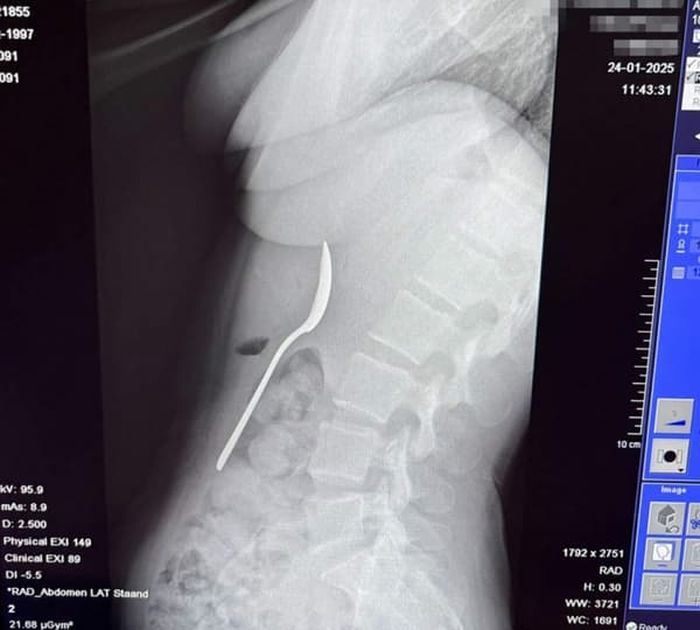

인터넷을 검색해본 레이미 씨는 상황이 매우 심각하다는 것을 깨닫고 급히 응급실로 향했습니다. 엑스레이를 찍어보니 정말로 기다란 숟가락이 그녀의 위장에 떡하니 자리 잡고 있었죠.

의사들은 숟가락이 너무 커서 자연적으로 배출될 수 없다고 진단했습니다. 이틀 동안 수술을 기다리는 내내 그녀는 갈비뼈 사이로 숟가락이 부딪히는 소름 돋는 느낌을 참아야 했습니다.

다행히 위를 절개하는 큰 수술 대신 내시경을 통해 숟가락을 꺼내는데 성공했습니다. 내시경 과정에서 약간의 출혈이 있었고 식도가 상해 며칠간 고생했지만 다행히 영구적인 손상은 없었는데요.